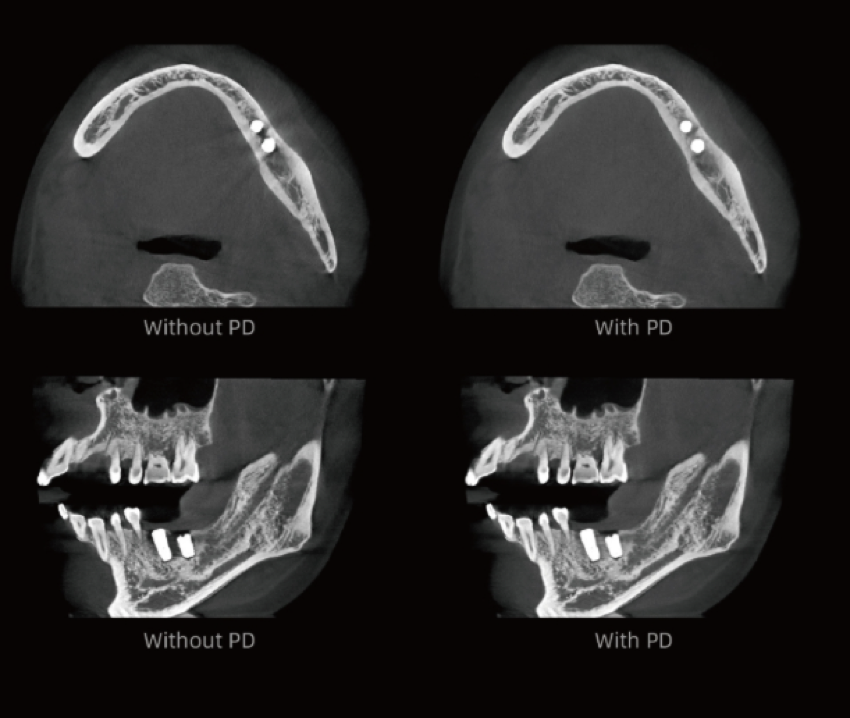

Algoritmo PD – Alta resolução espacial em TC até 2,8 lp/mm

Proporciona imagens com efeito de “textura natural”.

Previne eficazmente que pequenas lesões sejam ocultadas pela redução de ruído, reproduzindo com elevada fidelidade os detalhes do osso e dos tecidos moles.

Fornece aos clínicos informação diagnóstica mais precisa.